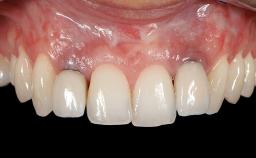

Soft-Tissue Volume Augmentation Using a Connective-Tissue Graft Harvested from the Maxillary Tuberosity

In 1983, a 51-year-old non-smoking patient was referred for the treatment of moderate chronic periodontitis. At the initial examination, 47% of sites exhibited probing depths of 4 to 6 mm. Periodontal therapy consisted of initial periodontal treatment including oral-hygiene instructions and supra- and subgingival debridement, followed by periodontal surgery to eliminate residual pockets.

Prosthesis Type FDP

Soft Tissue Anatomy Intact Defective